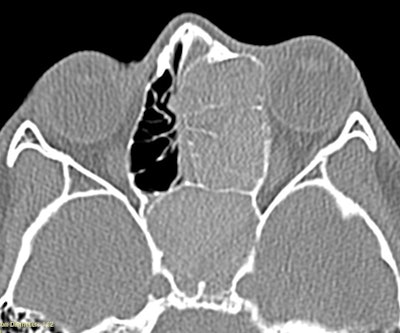

Clinically, AFRS often presents with substantial polyp burden and dense eosinophilic mucin with a “peanut butter” consistency (Figure 2A and B). CT can be helpful demonstrating classic findings of heterogeneous sinus opacification with areas of hyperattenuation and metallic-type “double densities” on soft tissue window (Figure 3).4 The disease process characteristically causes expansile changes to the paranasal sinuses, which can lead to expansion and erosion of the bony orbit, skull base, and facial skeleton (Figure 3).

Figure 3. CT demonstrating classic findings of heterogeneous sinus opacification with areas of hyperattenuation and metallic-type “double densities” on soft tissue window causing expansile changes to the paranasal sinuses and leading to expansion and erosion of the bony orbit, skull base, and facial skeleton.

Type 1 hypersensitivity to fungus is a Bent and Kuhn diagnostic criterion, yet the role of immunotherapy remains controversial without a clear benefit in decreasing disease recurrence or improving quality of life.1,2 We work closely with our allergy colleagues to determine whether immunotherapy will benefit patients’ allergy symptoms, but it is not standard practice. Finally, we have anecdotally observed therapeutic benefits of biologic agents targeting type 2 inflammation for some patients suffering with recalcitrant AFRS. The patient in Figure 3 underwent three surgeries including an endoscopic modified Lothrop procedure, and the disease was not controlled until a biologic was started. Although promising, there is limited data regarding the role of biologics specifically in AFRS.